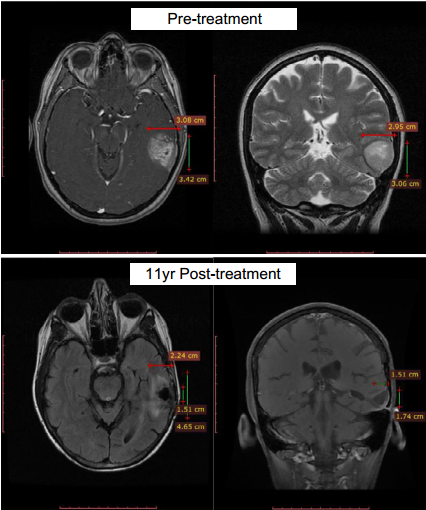

第一位超级响应者是一位多形性胶质母细胞瘤患者,先后接受过手术切除、局部的卡莫司汀化疗和放疗,复发后又使用替莫唑胺,保持了10年以上的完全缓解。

治疗11年后仍完全缓解